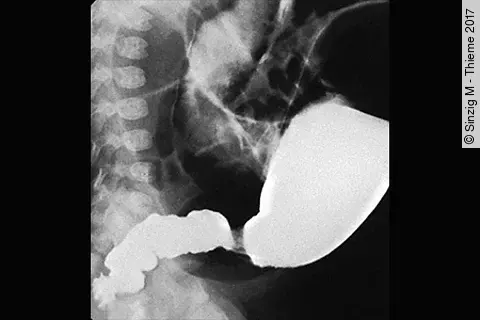

Endoskopisches LehrvideoPolyp im Divertikel

Unser neues Endoskopie-Video zeigt einen offensichtlichen Befund, der aber auch leicht zu übersehen ist. Welcher das ist und welche Methode zur Behandlung angewandt wurde, präsentiert PD Dr. Jochen Weigt vom Uniklinikum Magdeburg.